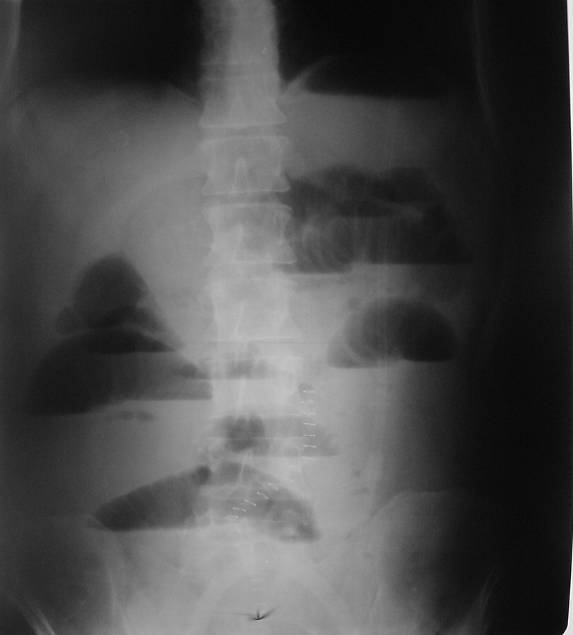

Konvansiyonel Radyoloji

• Direkt grafiler genellikle akut karın sendromu varlığında ya da akut tıkanıklıkta.